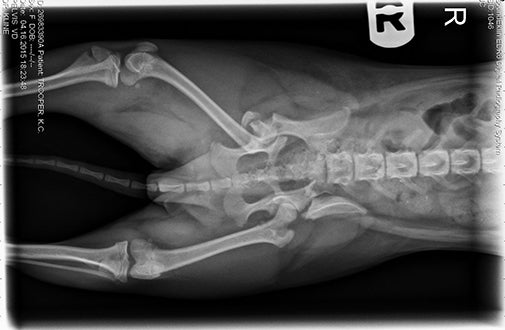

At the ASPCA Animal Hospital, Director of Surgery Dr. J’mai Gayle examined K.C. and noted that she had severe pelvic and leg fractures, along with neurological deficits associated with her injuries. “She was in significant discomfort,” Dr. Gayle said. At the time, K.C. weighed less than five pounds.

During K.C.’s two-week stay in the hospital, Dr. Gayle surgically repaired her fractured bones using plates, screws and wires. The petite pup also received medication to help ease her pain. “Despite all of her injuries, this little dog never offered to bite and was willing to accept all treatments without any hassle,” Dr. Gayle said. But K.C.’s stay in the hospital included more than medical treatment—it also led to her very first meeting with Jennifer.